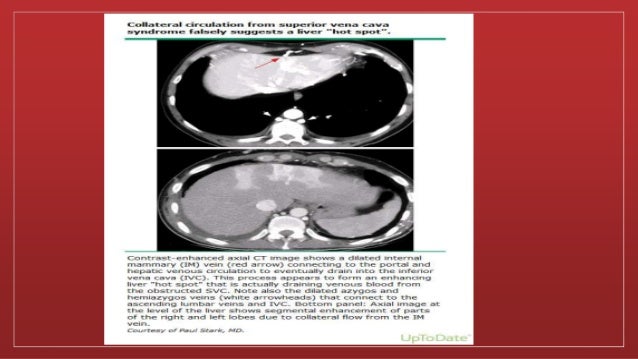

▪ Contrast-enhanced blood from the collateral circulation draining

into the inferior vena cava can simulate the appearance of a liver

"hot spot" on CT

Contrast enhanced chestCT ▪ Defines the level and extent of venous blockage. ▪ Identification of the underlying cause of venous obstruction. ▪ Identify and map collateral pathways of venous drainage ▪ Presence of collateral vessels on CT is a strong indicator of SVC syndrome, Specificity of 96 percent and sensitivity of 92 percent. ▪ Contrast-enhanced blood from the collateral circulation draining into the inferior vena cava can simulate the appearance of a liver "hot spot" on CT